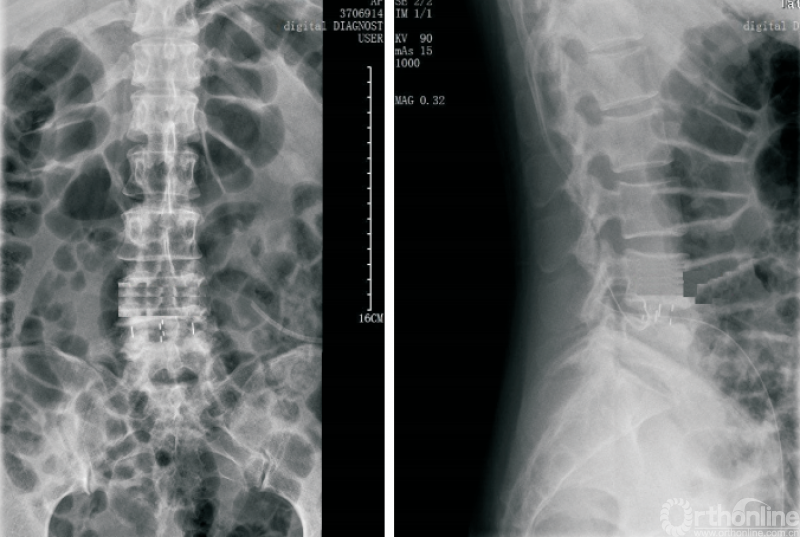

终板塌陷和融合器沉降(图6)是Stand-aloneOLIF的常见并发症,也是导致术后翻修的重要预测因素。融合器沉降与终板强度、手术操作以及解剖稳定性相关。终板硬化及形态平衡能够降低融合器沉降的发生率[36]。

图6 OLIF术后融合器沉降

LIU等[37]研究发现,在MRI影像中有Modic改变以及CT影像提示终板硬化的患者终板沉降的发生率明显低于其他患者。术中选择合适的融合器以及良好的脊柱稳定性也有利于降低融合器沉降的发生率[38]。ZHANG等[30]研究利用尸体标本模拟OLIF手术,通过研究生物力学特征、骨小梁微结构损伤等探索融合器与椎体骺环相对大小及位置对终板塌陷及融合器沉降发生率的影响,因此,在Stand-alone OLIF中选择合适的融合器对于减少终板塌陷及融合器沉降至关重要。

FANG等[39]通过构建有限元模型比较Stand-alone OLIF与OLIF联合后路钉棒系统固定两种手术方式后屈伸活动时终板应力等的变化,发现OLIF联合后路钉棒系统可降低屈伸活动时终板所承受的最大应力。术中终板损伤、间隙过度撑开等均会增大融合器沉降的发生风险。